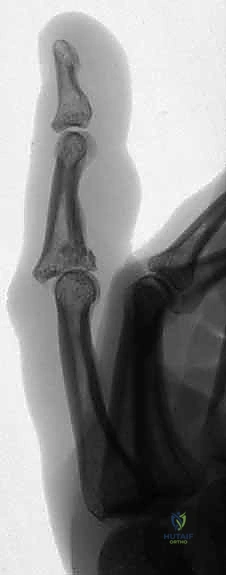

Figures 1A and 1B (TECH FIG 1A,B) show us marking the position for the first wire at the level of the center of rotation of the PIP joint, confirmed with the image intensifier.

-

Determine Entry Point: Aim to insert the wire 1 to 2 mm proximal to the marked center of rotation.

> SURGICAL WARNING: Aiming slightly proximal is crucial. The joint capsule reflects proximally from the articular margin. By staying 1-2mm proximal, we ensure the wire remains extracapsular. A distal wire, penetrating the joint capsule, significantly increases the risk of joint infection if pin track sepsis develops, leading to catastrophic outcomes. Conversely, placing this wire too far proximally in the diaphysis of the proximal phalanx will restrict full joint movement, defeating the purpose of a dynamic fixator. This balance is key. -

Initial Wire Insertion: Take your 1.1-mm K-wire and, under direct visualization and fluoroscopic guidance, initiate insertion through the skin and subcutaneous tissue. Aim for the center of the proximal phalanx in both PA and lateral planes. Ensure it is perpendicular to the long axis of the finger and parallel to the intended plane of rotation of the joint.

> PEARL: As you insert, you should feel the resistance of the cortical bone. Advance slowly, using a drill with a controlled, oscillating motion to prevent thermal necrosis of the bone. -

Fluoroscopic Confirmation (Partial Insertion): Insert the wire partially through the proximal phalanx, ensuring it crosses the head of the proximal phalanx. Immediately check its position with both true posteroanterior (PA) and lateral projections on the image intensifier.

Figure 1C (TECH FIG 1C) confirms the wire inserted across the head of the proximal phalanx, verified on the image intensifier, before further advancement.

- Finalize Proximal Wire Placement: Once confirmed, advance the wire fully through the bone, ensuring equal lengths are present on either side of the finger. This symmetry, while less critical for the proximal wire, will serve as a useful guide for balancing the distal wire later.